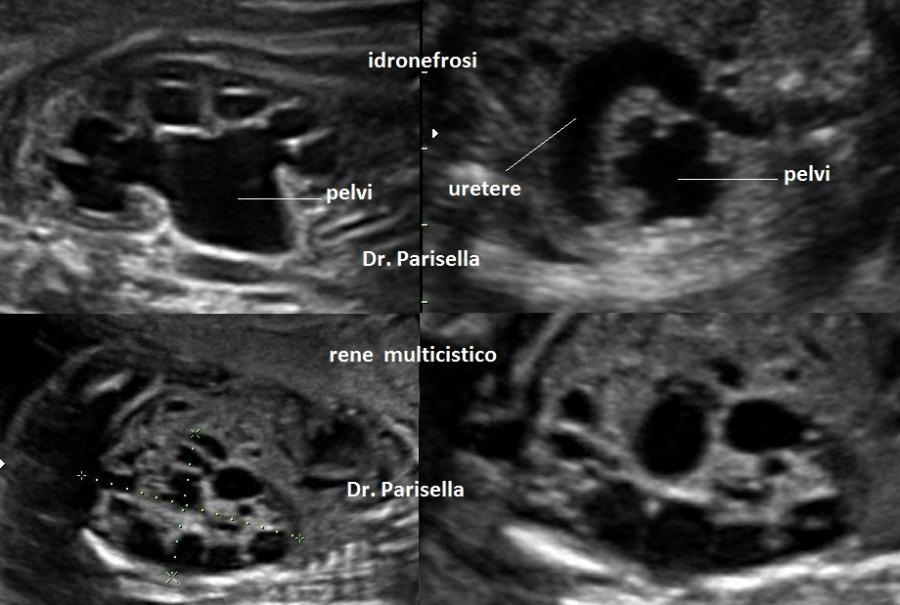

anomalie urinarie

agenesia renale bilaterale